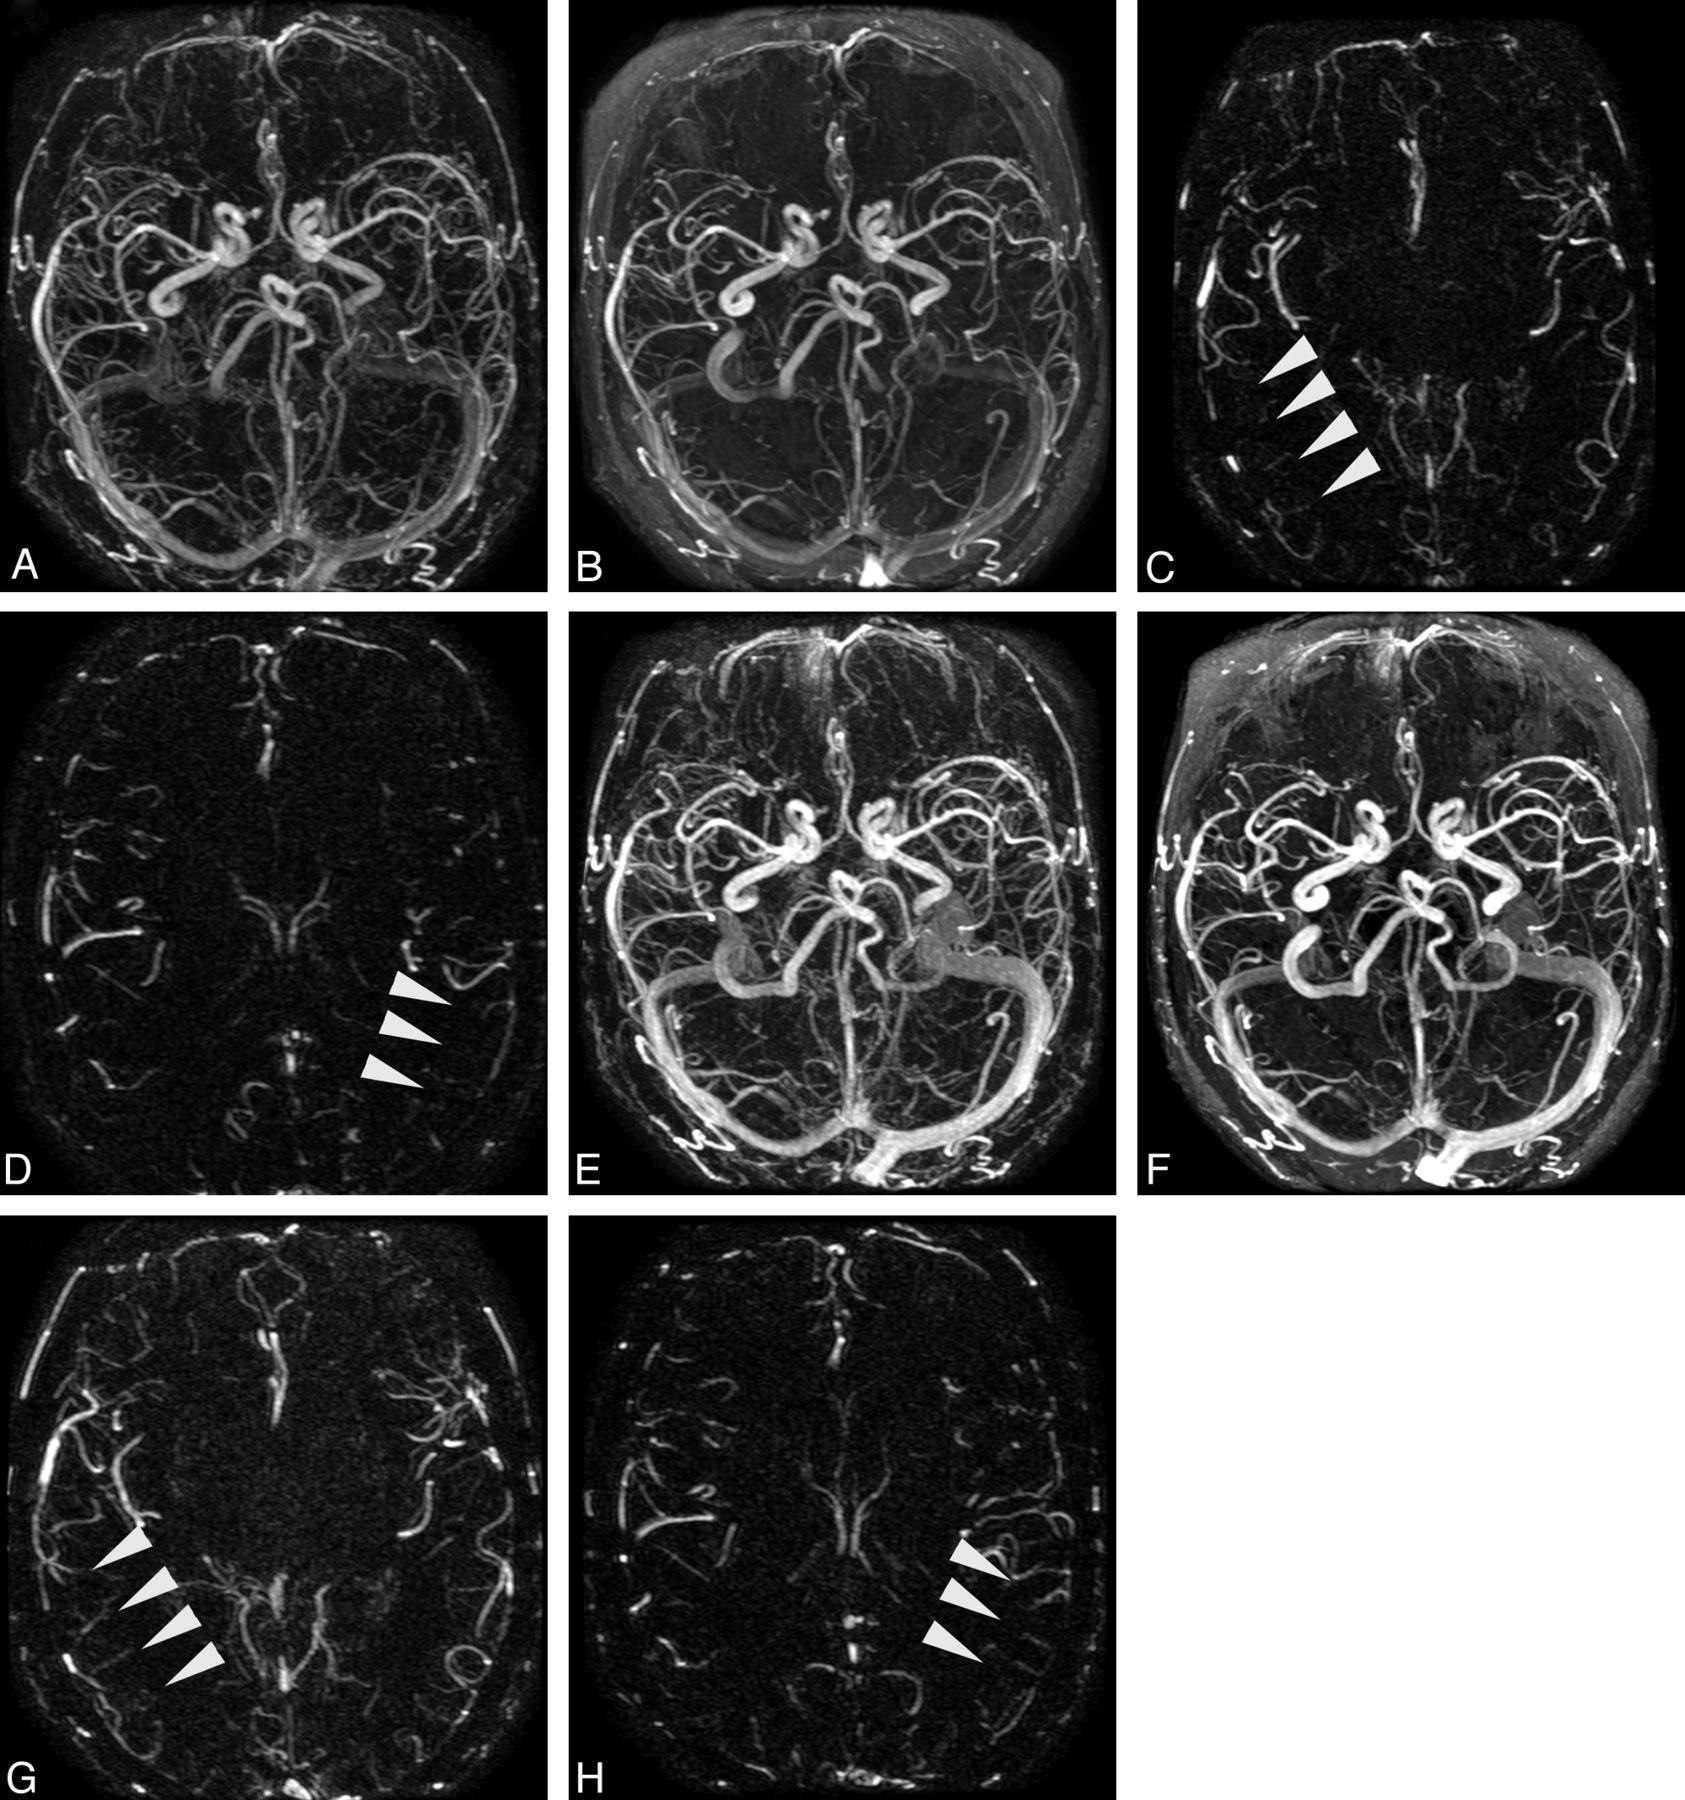

Patient (68-year-old woman) undergoing successive TR-MRA spaced approximately 1 year apart, for evaluation of angiographically documented indirect dural arteriovenous fistula (arrow). Images in A–C were obtained with injection of SCA; images in D–F were obtained with BPA. Early arterial (A, D), late arterial (B, E), and venous (C, F) axial MIP phases are presented as indicated. Qualitatively superior time-resolved angiography was scored for all temporal phases and arterial segments, with consideration to diagnostic confidence and vessel-background contrast. Note the generally delayed arrival/temporal phases with the slower administration rate of BPA.

Whereas significant differences in quality were not identified between the agents for characterization of the superficial venous segments, venography of the deep system demonstrated significant superiority of BPA over SCA on subtracted and unsubtracted volumes (unsubtracted 2.92 ± 0.27 versus 2.74 ± 0.44, P = .016; subtracted 2.8 ± 0.4 versus 2.6 ± 0.53, P = .037, respectively).